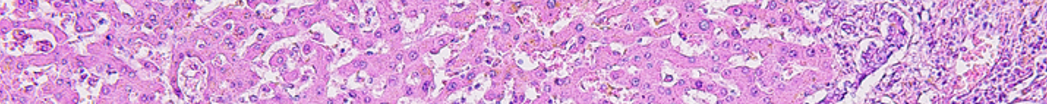

The transition from child to adulthood care is a critical period to navigate in continuity of health care. This is especially true for children with eosinophilic esophagitis (EoE), who are likely to have ongoing and evolving symptoms and who may develop complications over time. Approximately 30% to 50% of children transitioning to adulthood report symptoms of dysphagia several years after EoE diagnosis, with many requiring interventions such as dilation. Clinicians must be aware of best practices for shared decision-making during care transitions as children with EoE reach adolescence and early adulthood.